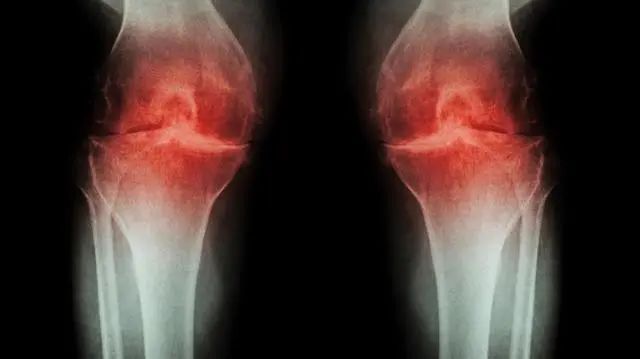

膝关节骨关节炎、退行性改变、骨刺,如何防治?

骨关节炎是由于衰老、肥胖、炎症、创伤、关节对线不良、代谢异常、性激素水平及遗传等原因,导致以关节软骨的变性、破坏,软骨下骨肥反应和关节边缘骨赘(骨刺)形成为特征慢性关节病。主要表现为关节疼痛和活动不灵活,活动受限,X线表现为关节间隙变窄,关节边缘钙化和增生,胫间脊变尖等,常伴有肌肉无力、韧带松弛、关节对线不良、轻度滑膜炎和半月板变性等症状发生。

②X线关节边缘有骨赘形成;